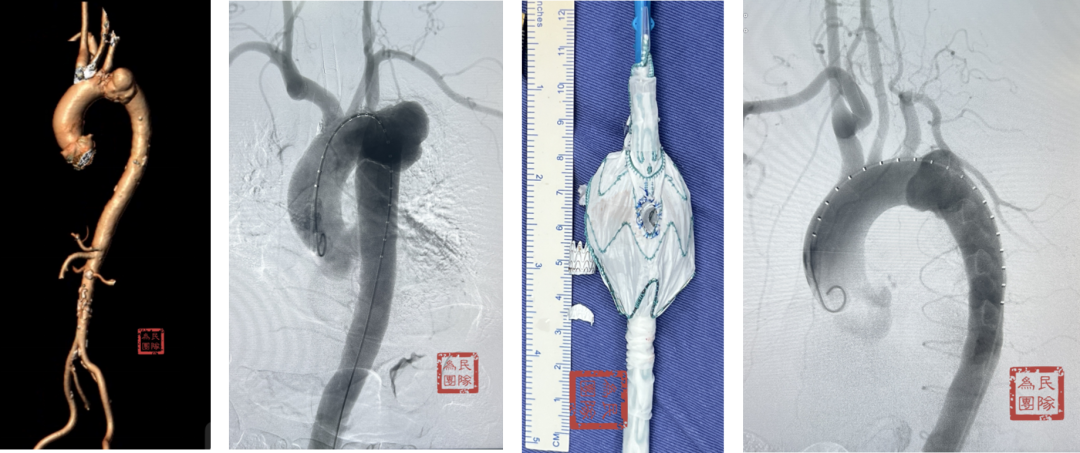

【分支支架开窗技术】未来趋势的探索

分支支架是指自带弓上分支的主动脉覆膜支架,尤其是三分支支架的使用促进了全腔内修复术的重大进展。

Castor支架是目前国内唯一上市的分支支架产品,研究表明术后长达92个月随访,并发症发生率为0.035%。可结合左锁骨下动脉开窗技术,也可重建左颈总动脉血运,适用于Z2和Z3区病变。

弓部动脉瘤:Castor联合内嵌分支LSA预开窗术,目的为防内漏

避免转流的复杂病例:Castor+原位及预开窗(免转流三开窗)治疗弓部动脉瘤